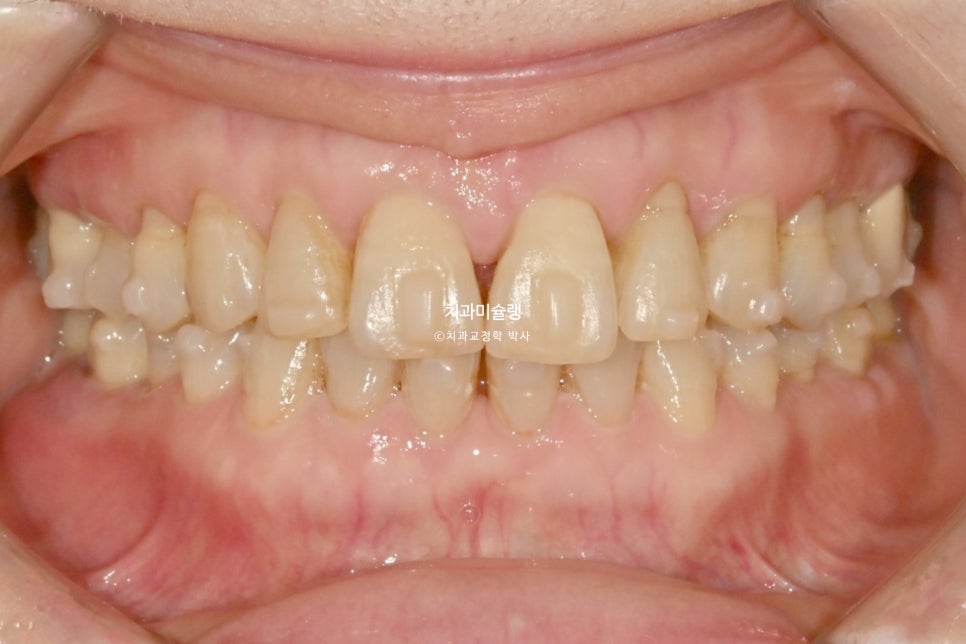

2025년 2월, 치료를 마무리 했습니다.

총 치료기간은 11개월입니다.

어금니 교합은 그대로 유지되었으며 돌출되고 벌어진 앞니는 깔끔하게 제자리를 찾았습니다.

앞니 부분교정이지만 한결 깔끔해진 미소가 돋보입니다.

튀어나오고 솟아내려온 앞니가 들어가며

입술 다무는게 조금 편해졌다고 하십니다.

치근흡수는 없으며, 기울어져있던 앞니 치축이 개선되었습니다.